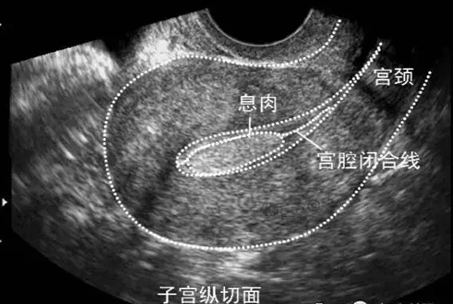

子宫内膜息肉是长在子宫里的“多肉”,亦是子宫内局部内膜过度生长的产物。如果说子宫内膜是土壤,那么息肉可被视为“杂草”。子宫内膜息肉作为妇科的一种常见病,是由内膜腺体、间质、血管组成,可以单发,也可以多发。舌形或椭圆形,形状及大小变化较大,小的约1~2毫米,大的可以充满宫腔。蒂部长度不一,具有较长蒂部者,息肉可以通过扩张的宫颈管突向宫颈外口或阴道内。好发于宫底部、宫角或子宫后壁。单发较小的息肉一般无临床症状,多数是B超检查或宫腔镜检查时发现。

临床上B超是诊断子宫内膜息肉的首选检查。宫腔镜检查同时取病理组织活检,是诊断子宫内膜息肉的金标准,也是目前较好的治疗手段。